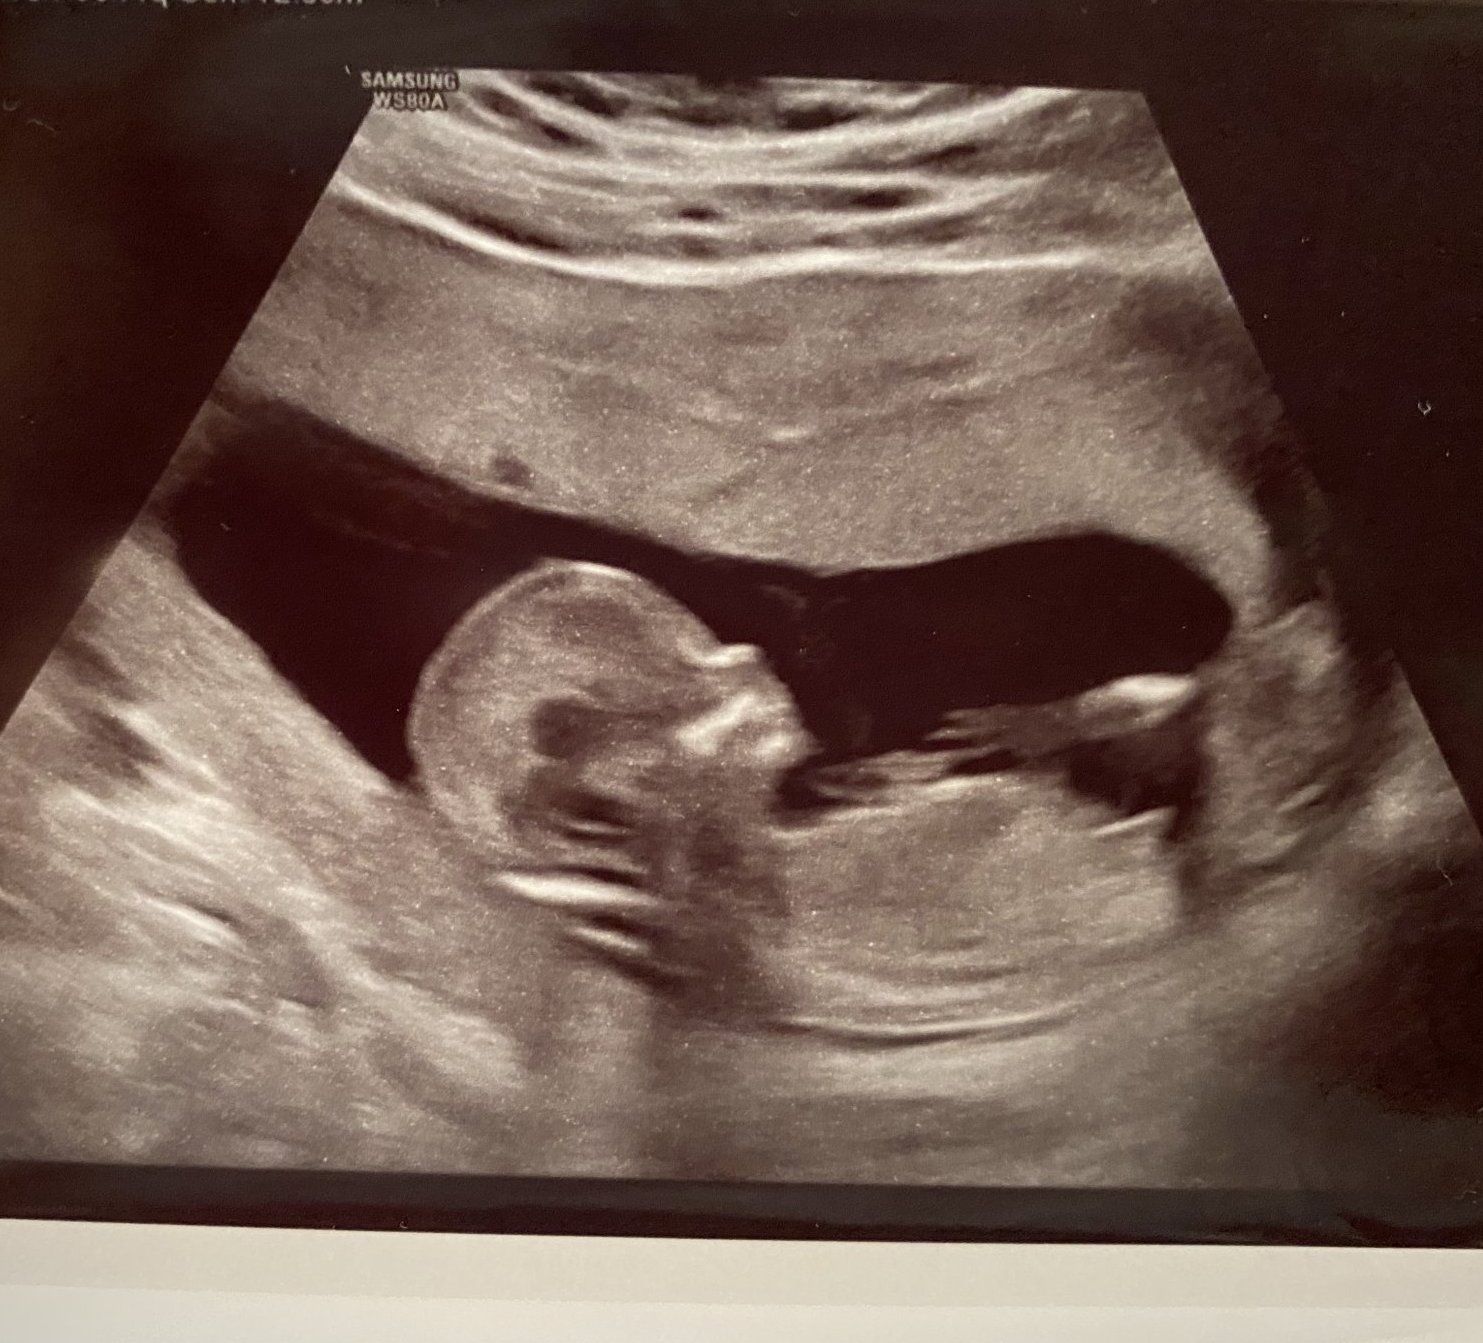

Феталната морфология е специализиран ултразвуков преглед, който се провежда между 20-та и 24-та седмица от бременността. По време на него се прави подробен преглед на бебето, включително оценка на неговата анатомия, развитие и функции. Обикновено се извършва по време на бременност за оценка на развитието на бебето в утробата и включва подробен анализ на анатомията на бебето, както и оценка на различни параметри, които могат да показват наличието на генетични аномалии или други проблеми.

Здравейте! Записвам се към бъдещите декемврийски мами и аз. На 28год от Стара Загора. Термин 14.12. Имам си вече едно октомврийче 2014, което обаче от много бързане стана септемврийче 😀 В 14+4г.с. съм. Миналата седмица минах на първа ФМ и човекът е перфектен, обаче пол не ми казаха, но както казах и на Док “Щом още няма пишка, няма и да има” 😀